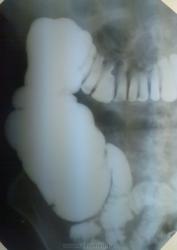

Учитывая такую картину и динамику принято решение о проведении ирригоскопии.

Ничего особенного, фрагмент прилагается. Но, поскольку клиника вздутия ПЕРИОДИЧЕСКИ сохраняется, прооведена еще одна обзорная рентгенограмма.